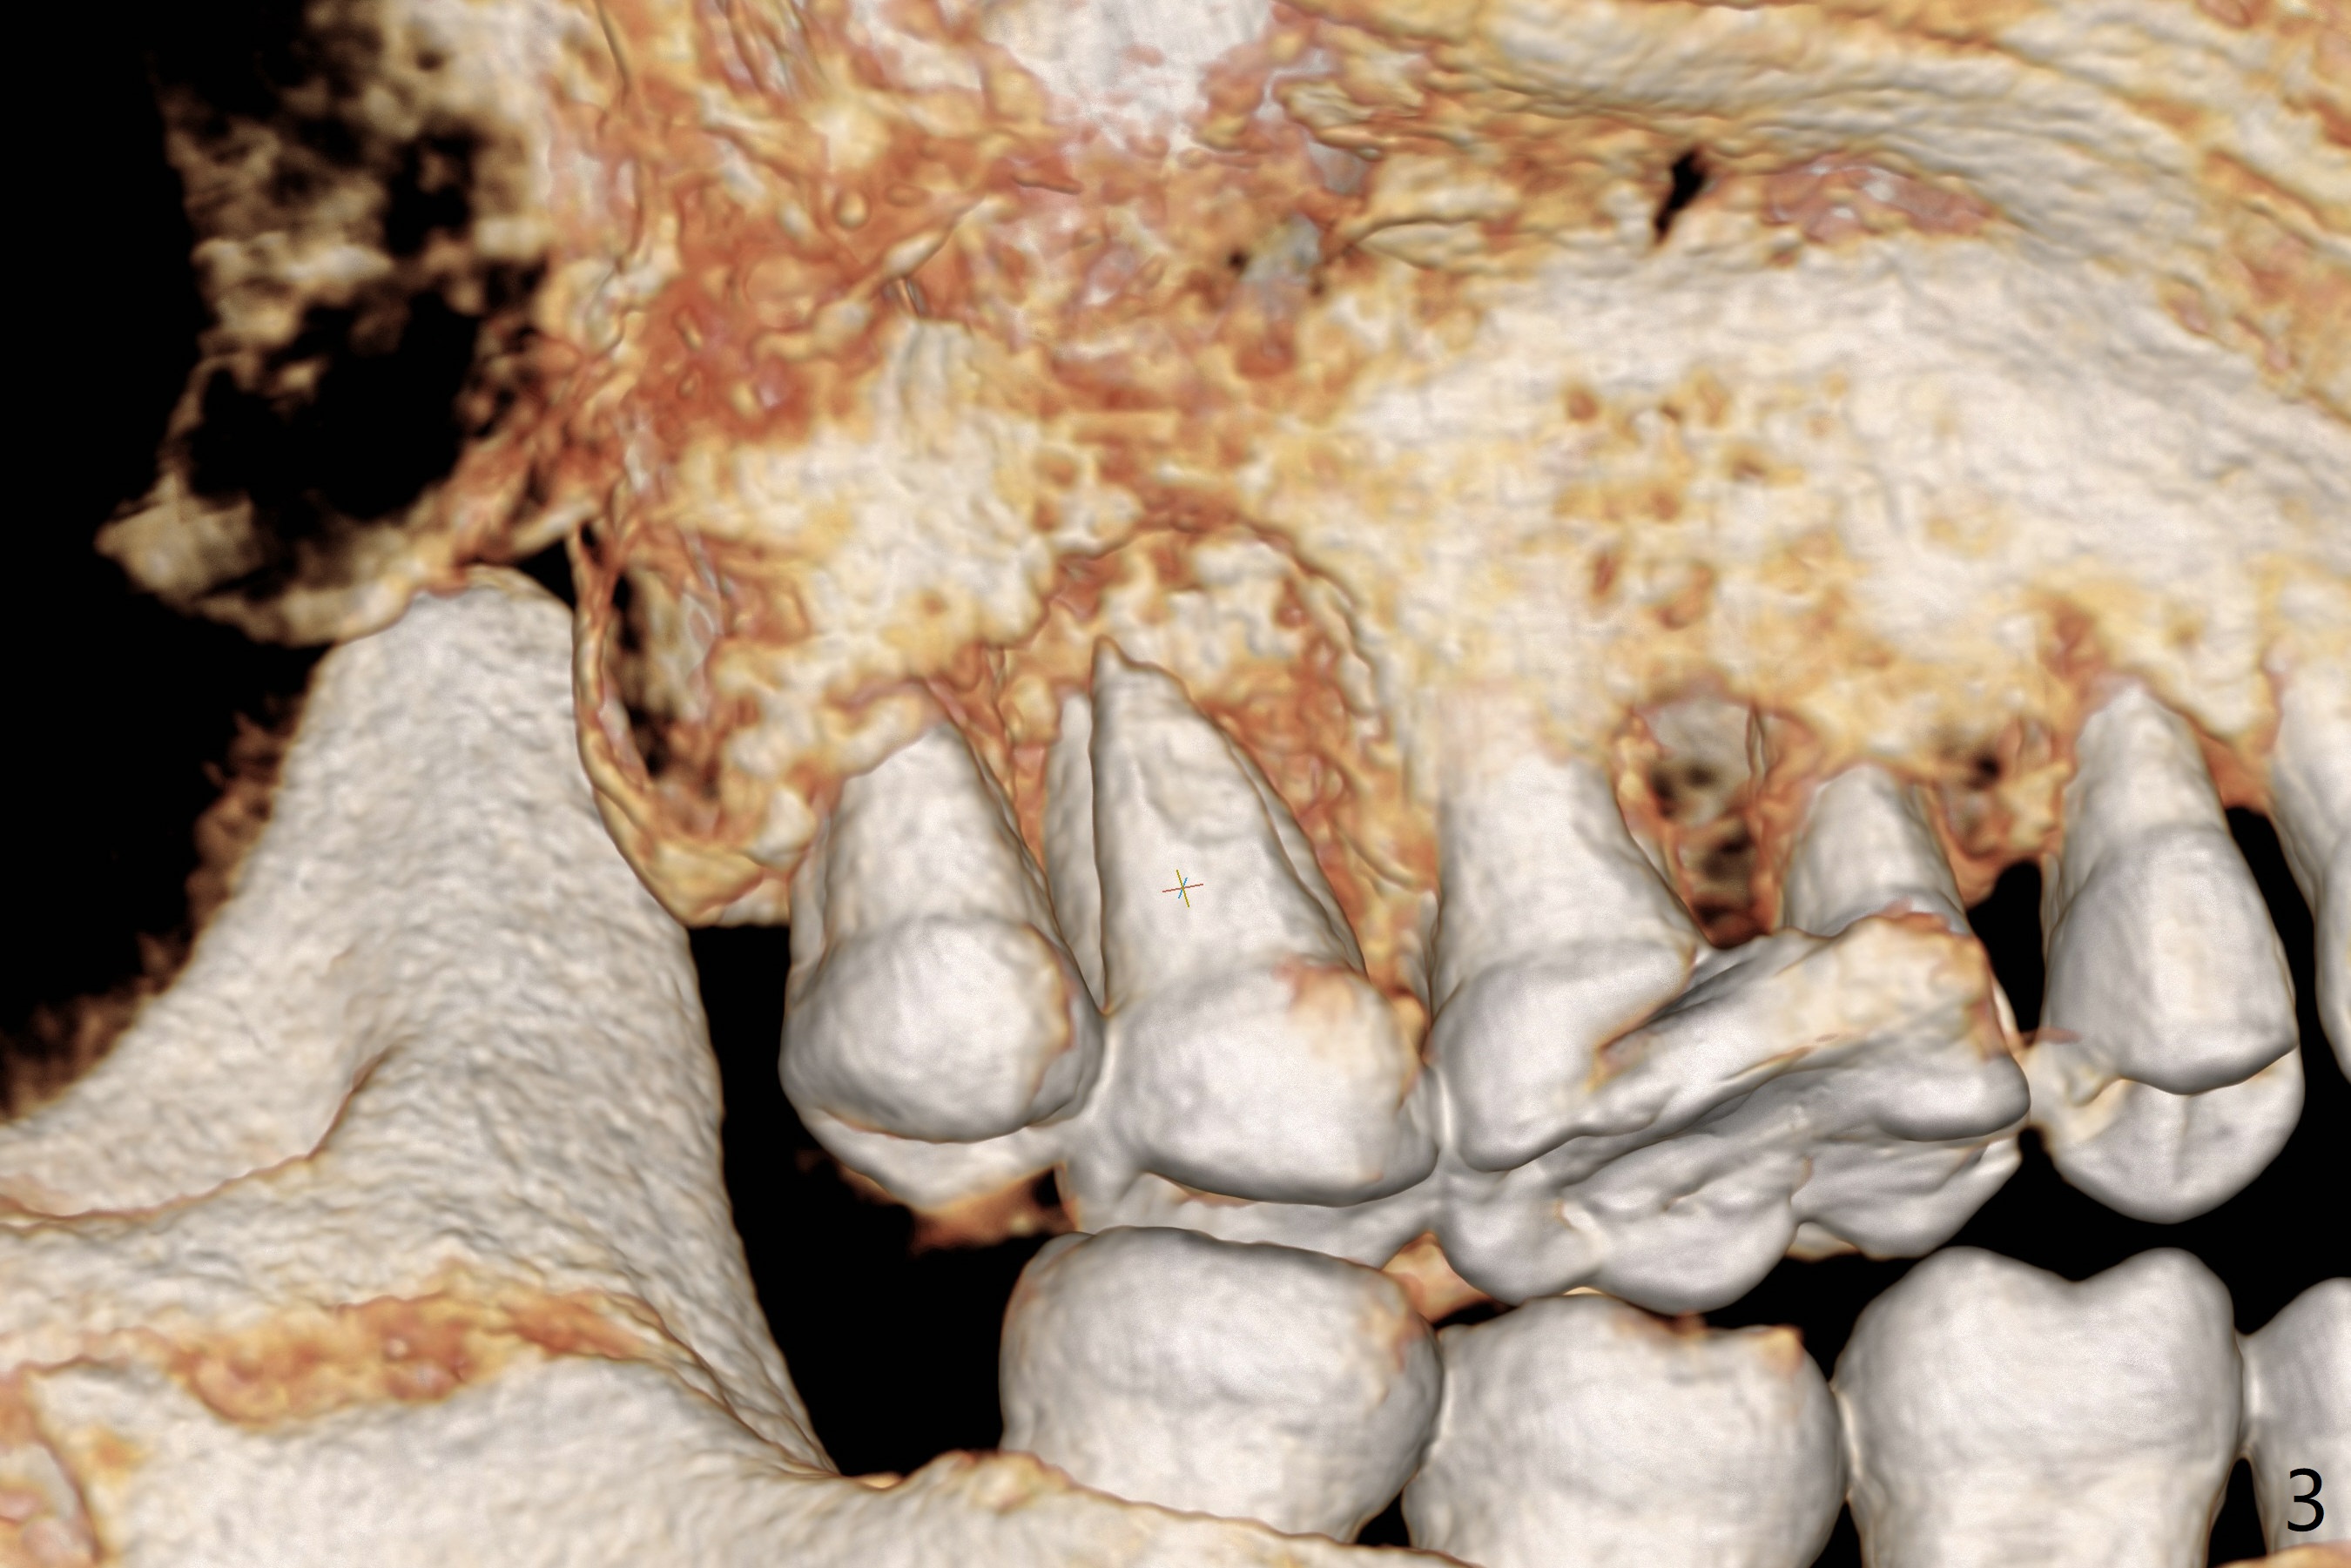

The 54-year-old woman (bruxer) agrees to have implant because of the loose tooth at #15 (Fig.1 (pan)). Since the left sinus membrane is thickened (Fig.2 *), an immediate implant will not be penetrated the sinus floor if primary stability is acceptable. If the sinus lift has to be done, PRF membrane/plug will be prepared. The large periradicular radiolucency is associated with the vertical palatal root fracture (Fig.3). A 5x8.5 mm implant is placed as buccal as possible with guide (Fig.4).